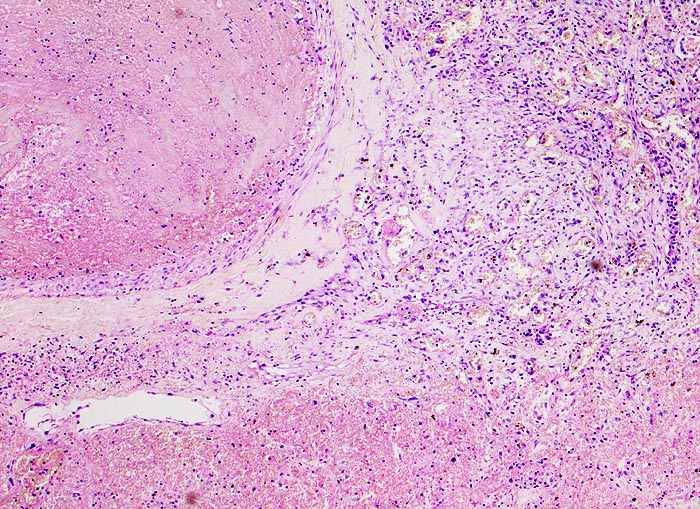

• Scharf begrenzte dreiecksförmige hämorrhagische Nekrose des Lungenparenchyms.

• Lungengerüst erhalten im Randbereich der Nekrose, nicht mehr erkennbar im Zentrum.

• Pulmonalarterienast mit nicht wandhaftendem Thrombembolus am Rand des Infarktes.

• Frischblut im Lumen des begleitenden Bronchiolus.

• Pulmonalarterienast mit Strickleiter.